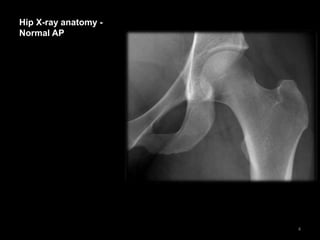

Hip X-ray anatomy -

Normal AP